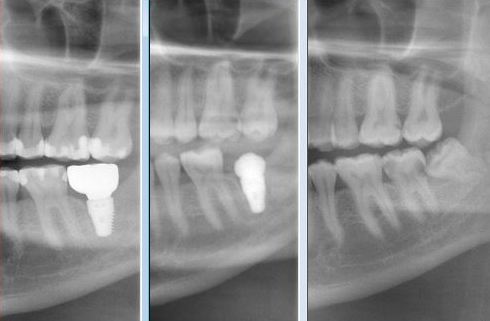

IMMEDIATE LOWER MOLAR REPLACEMENT

This type of cases Dr. Andrews encounters on a regular basis.

A 30 year old was concerned with the discomfort next to his impacted wisdom tooth and pain associated with cold and hot temperatures around the decayed back teeth.

After thorough dental examination Dr. Andrews recommended to extract the wisdom tooth (#17) and the second molar (#18) due to severe decay and poor prognosis for both teeth and to replace the second molar (#18) with a dental implant.

During only one 45-minute surgery both teeth were removed, a minor bone graft was placed and a wide-diameter (7 mm) dental implant was immediately inserted to replace the second molar. Four months later , #18 implant was restored with an all-ceramic crown.

Revolutionary digital scanning technology and CAD/CAM fabrication process had been used by Dr. Andrews to create an ideal emergence profile, ideal bite and natural anatomy for the crown.

Cavities on other teeth were treated with mercury-free, bio-mimetic white composite fillings.